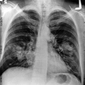

Mezenterik lenf nodları, karın boşluğunda, mezenter adı verilen, ince bağırsakları ve kalın bağırsakları destekleyen dokuda bulunan lenfatik yapılar olarak bilinir. Bu nodlar, bağışıklık sisteminin önemli bir parçasını oluşturur ve vücudu enfeksiyonlardan korumada kritik bir rol oynar. Mezenterik lenf nodları, bağırsaklardaki besin maddelerinin emilimi ve bağışıklık tepkileri ile ilgili işlevlere sahiptir. Mezenterik Lenf Nodu Yapısı ve FonksiyonuMezenterik lenf nodları, lenfatik sistemin bir parçası olarak, lenf sıvısının filtrelenmesini sağlar. Bu yapıların temel işlevleri şunlardır:

Bu hastalıklar, mezenterik lenf nodlarının büyümesine, iltihaplanmasına veya disfonksiyona yol açabilir. Tanı YöntemleriMezenterik lenf nodlarının değerlendirilmesi için çeşitli tanı yöntemleri kullanılmaktadır. Bu yöntemler arasında:

Bu yöntemler, doktorların lenf nodlarının boyutunu, şeklini ve yapısını değerlendirmesine olanak tanır. Ayrıca, olası enfeksiyon veya kanser gibi durumların teşhis edilmesine yardımcı olur. Mezenterik Lenf Nodu Tedavi SeçenekleriMezenterik lenf nodlarındaki hastalıkların tedavisi, altta yatan duruma bağlı olarak değişiklik gösterir. Tedavi seçenekleri arasında: